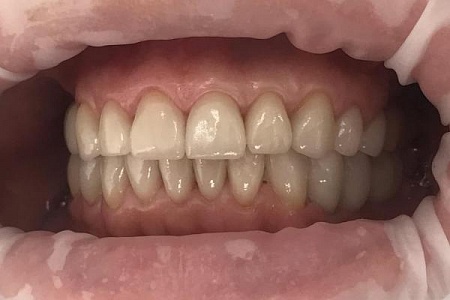

Работы наших врачей